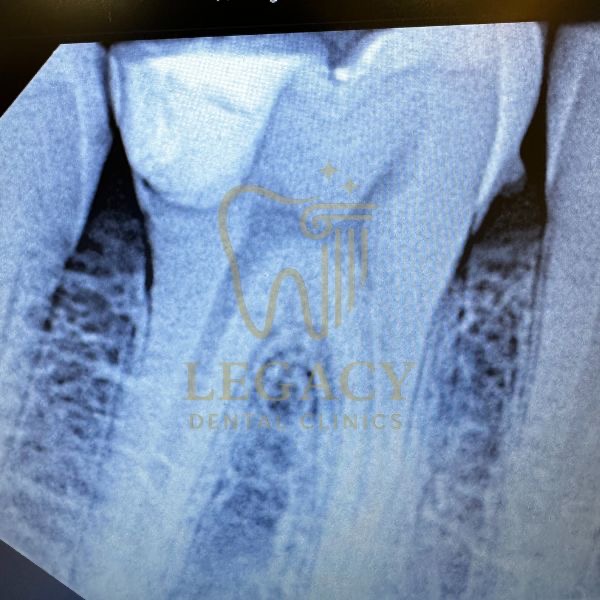

حالة زراعة فورية لسن أمامي - د.عمر نافوخ